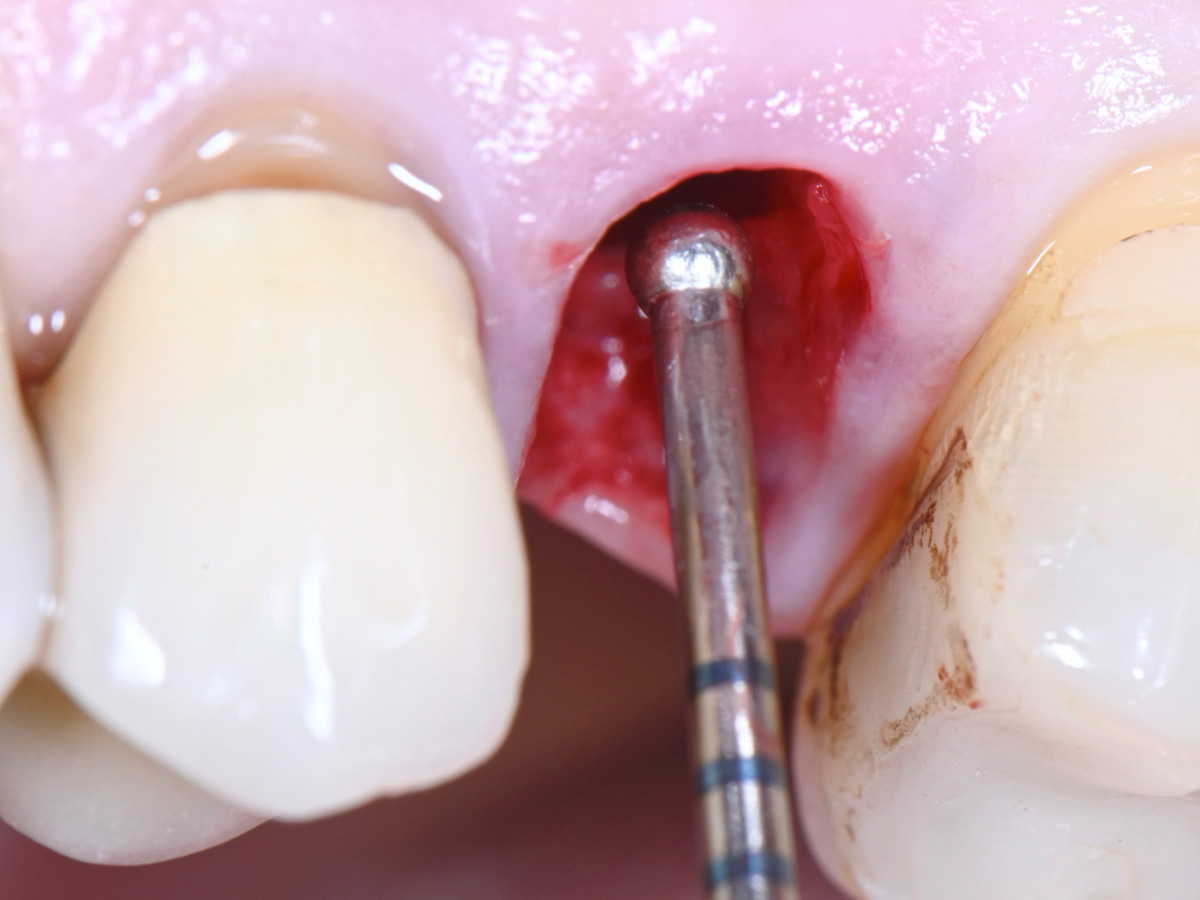

Abbildung 7

Sondierung der Extraktionsalveole mit einer Kugelsonde